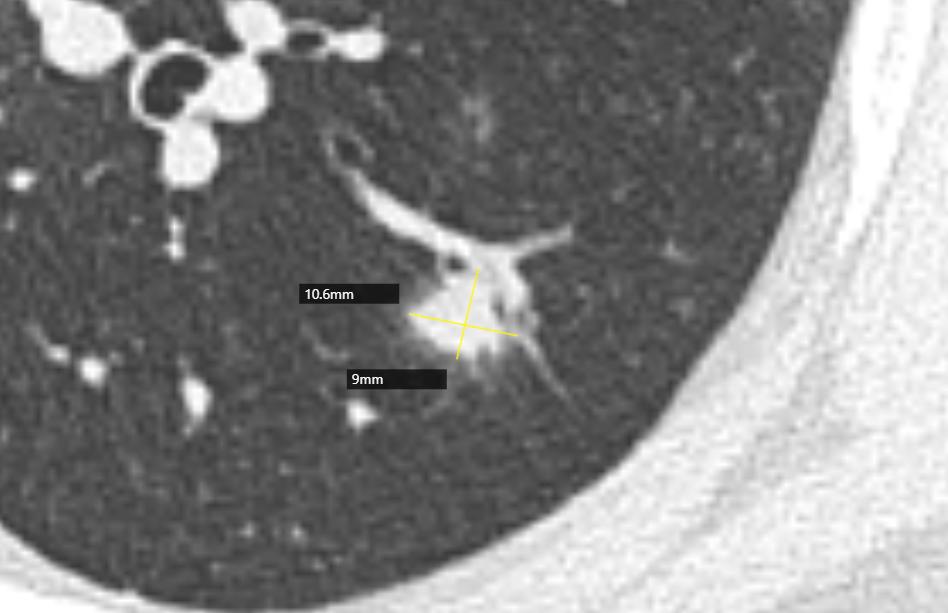

影像学是建立在高清影像的基础上的诊断,首先我们的图片要清楚,以下是患者家属提供的DICOM数据,分析时得到的图片。很多时候诊断不清楚,就是因为影像资料不清楚。

通过以上图片,病灶确实为实性结节,大小约1.0cm×0.9cm×1.0cm,呈浅分叶,周边可见毛刺,可见小血管穿入,但是影像学还是有一些不符合恶性肿瘤的特点:

1.病灶周边有一些渗出性改变。

2.相对1cm大小的肺结节来说,周边的毛刺有点长。

3.病灶及周边有扩张的支气管影。

4.病灶周边血管明显有贴边征象。

5.病灶两个月前 大小约0.6cm×0.8cm,这一点还是很重要的,如果我们在看诊过程中只带胶片,很难比较的。

6.双肺还有多发类似实性小结节,病灶均较为模糊,虽然是实性结节,但相对更趋于新发的可能,没有纤维化。